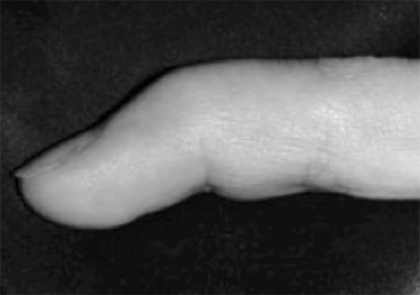

Aquesta malaltia es caracteritza per una contractura de la palma i dits de la mà deguda a una proliferació del col·lagen.